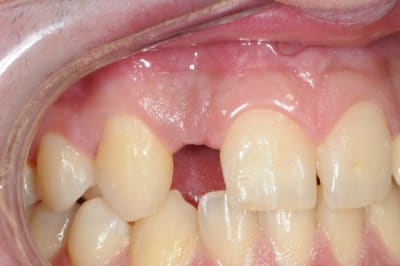

> tiens voilà un cas comme j'en vois assez régulièrement...10 agénésies....

> Photo prise avec mon portable désolé

il est bien ton portable

mef à la 12 os pas toujours sympa avec les dentistes....